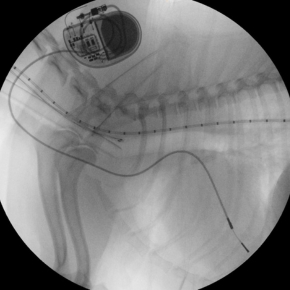

Pacemakers are lifesavers for many of our canine patients, and whilst the knee-jerk reaction is often to avoid future anaesthetic procedures altogether, you may be surprised to hear that it is more straightforward than you think. Below is a concise, step-by-step framework you can follow the next time a pacemaker patient lands on your surgical list.

Has the pacemaker been fitted in the last 10 weeks? Unless it’s an emergency, postpone elective anaesthesia. During this “bedding-in” window the lead tip is still fibrosing into the right-ventricular endocardium and infection risk remains higher.

If a routine cardiology check-up is due, schedule it before the anaesthetic. We’ll confirm pacemaker battery status, capture thresholds and importantly – screen for any evolving structural disease that might require you to tweak your drug choices.